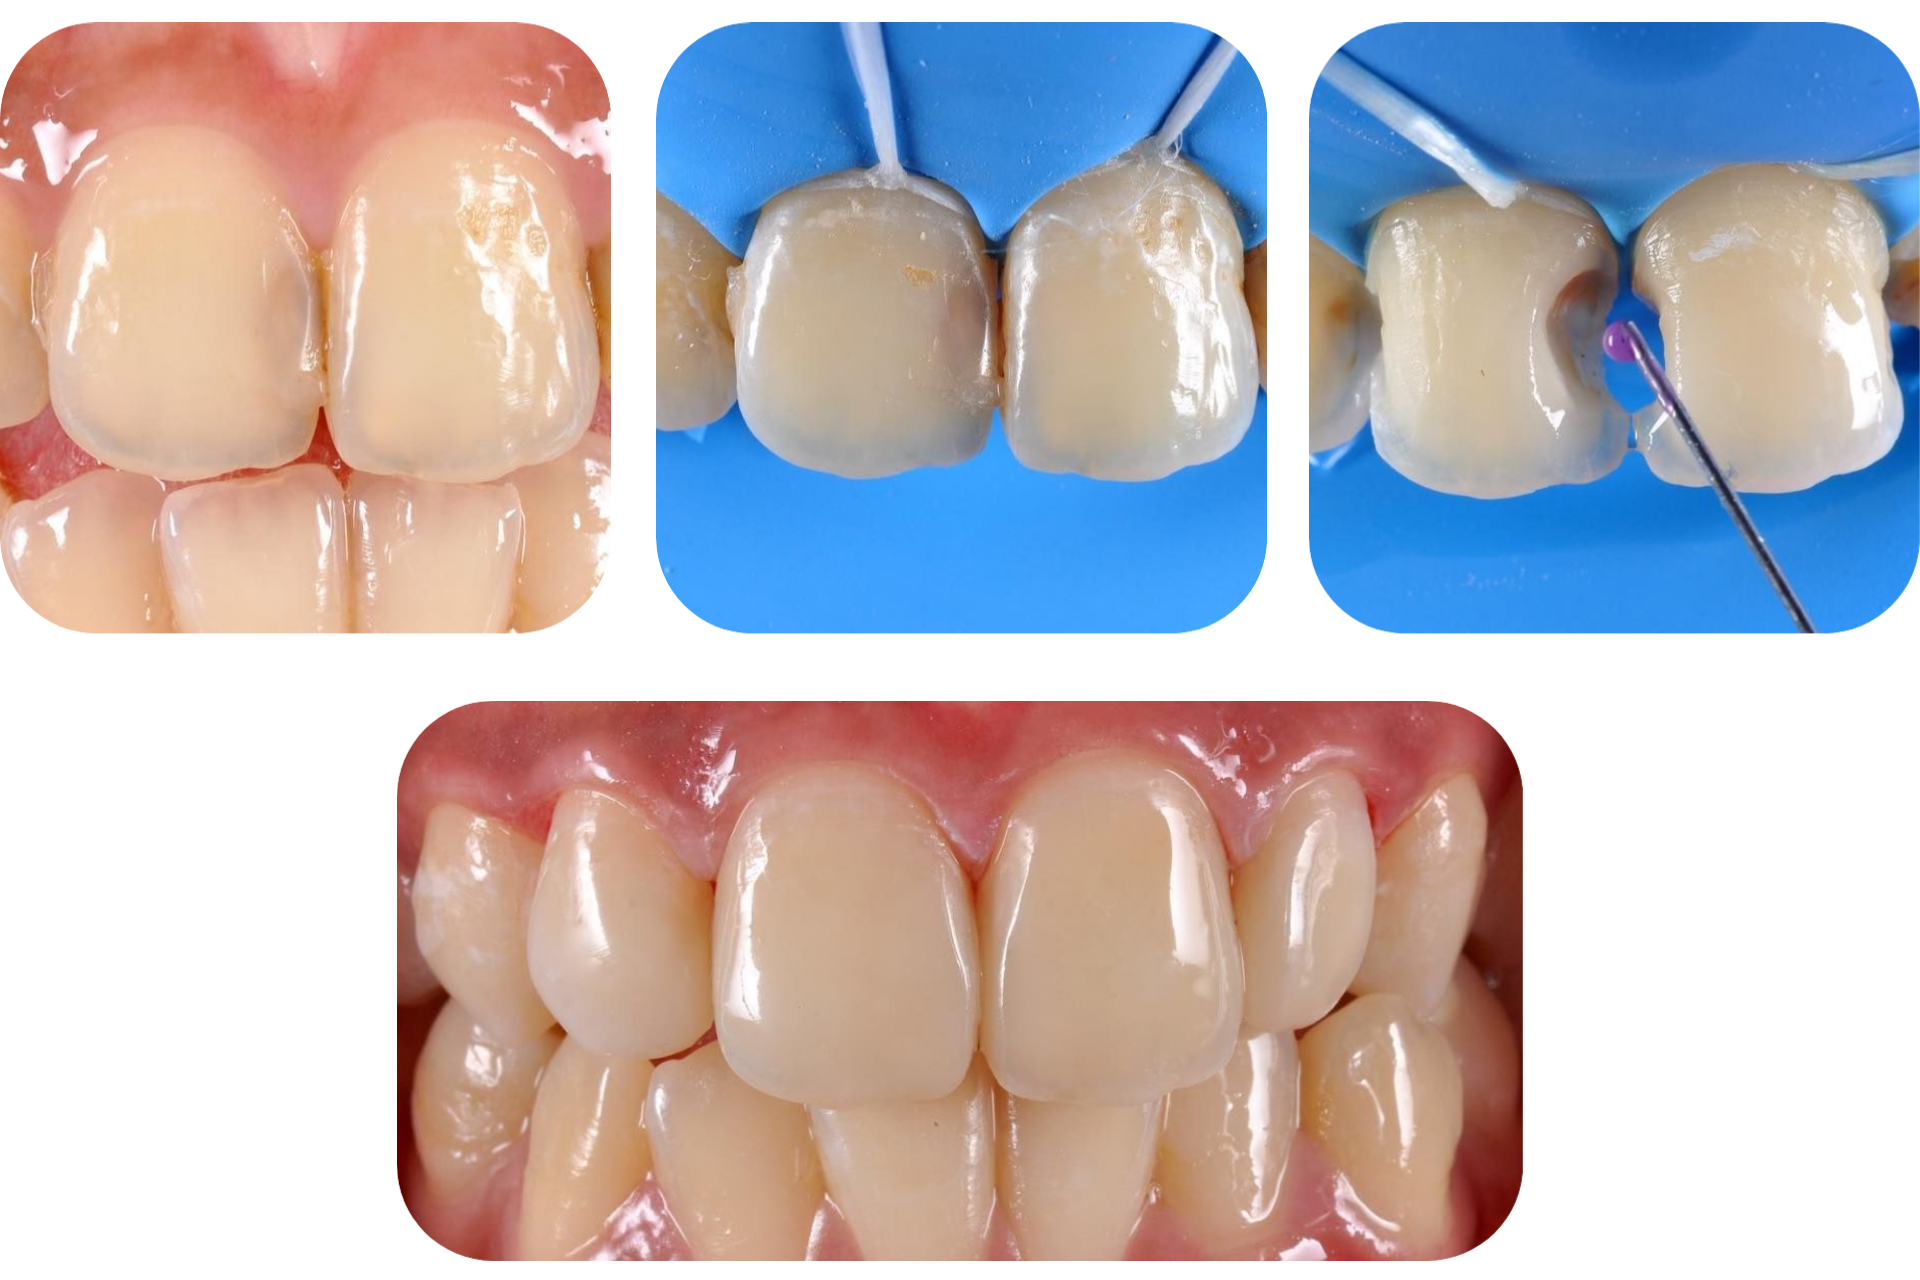

Реставрация

Позволяет устранить различные визуальные дефекты: трещины, сколы, диастемы, изменение цвета эмали и др.

Как лечим?

1. Восстанавливаем эстетику жевательных или передних зубов за один визит к стоматологу.

2. В некоторых ситуациях используются ортопедические конструкции, например, виниры.

Безболезненное и комфортное лечение кариеса.

После

До

Лечение кариеса на жевательных зубах.